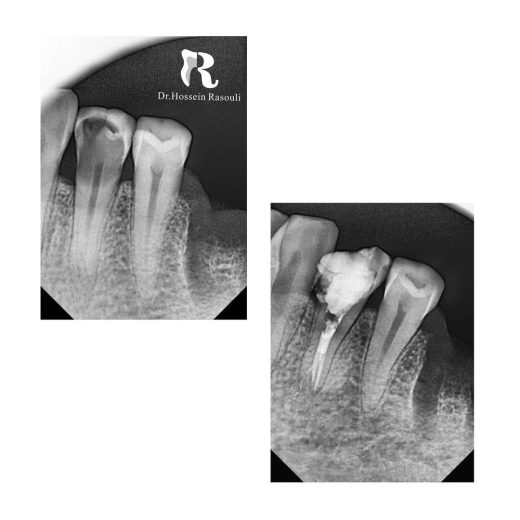

پرمولر سه کانال پایین

3 Canal Lower Premolar